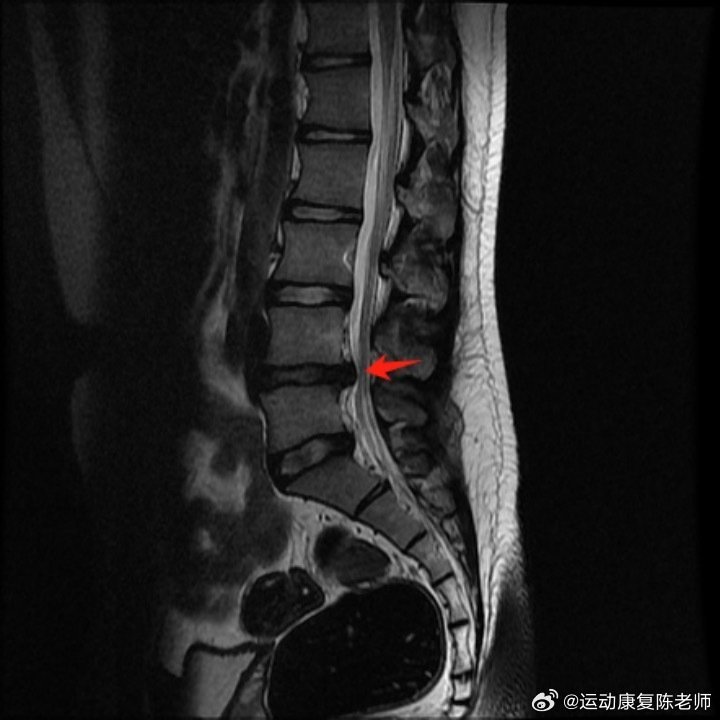

👉【腰椎间盘突出】图2.5随着病情的加重,腰椎间盘膨出可能进一步发展为腰椎间盘突出。此时,椎间盘纤维环在外力的作用下发生破裂,髓核组织从破裂之处突出,对脊神经根造成压迫,引发更为明显的疼痛、下肢麻木等症状。

腰痛可能表现为持续性钝痛或牵扯样痛,久坐、久站时发作,平卧时减轻。部分朋友还可能出现突发的腰部痉挛样剧痛,难以忍受。